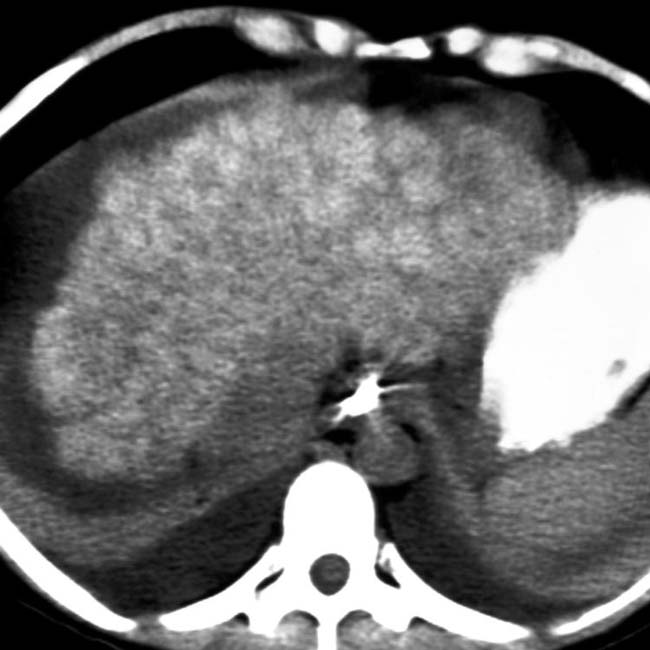

from radiologykey.com

Wilson Disease Radiology Key